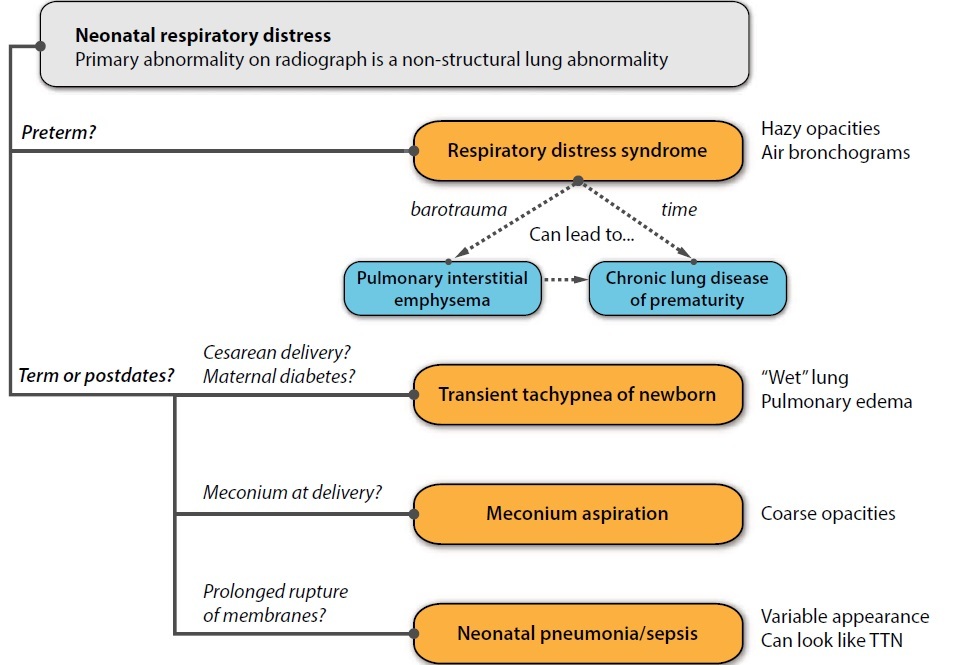

Despite this broad range, there are four classic differentials for a newborn with “medical respiratory distress” - that is, a baby that appears to be anatomically normal by radiograph (i.e., without cardiomegaly or thoracic mass), but has a diffuse pulmonary abnormality.

Transient tachypnea of the newborn (TTN)

Transient tachypnea of the newborn (TTN) is the most common cause of neonatal respiratory distress. It is caused by lack of clearance of fetal lung fluid.

Normally, prostaglandins dilate pumonary lymphatics to absorb excess fluid. When pulmonary fluid persists, TTN may result. The etiology of the excess fluid may relate to prostaglandin imbalance, potentially worsened by maternal asthma or diabetes, male sex, or Cesarean delivery (lack of vaginal “squeeze”).

Chest radiograph shows pulmonary edema, often with fluid tracking in the minor fissure.

Respiratory distress syndrome (RDS)/Hyaline membrane disease.

Respiratory distress syndrome (RDS), also called hyaline membrane disease, is the most common cause of respiratory distress in pre-term infants.

RDS is caused by insufficient surfactant (due to immature type II pneumocytes) and resultant decreased lung compliance.

Greater than 95% of cases are seen in pre-term infants born before 34 weeks. Less commonly, term babies born to diabetic mothers have increased prevalence of RDS.

Imaging is characterized by hazy pulmonary opacities, often with air-bronchograms. A key imaging feature that may be seen is decreased lung volumes if the baby is not intubated.

Pulmonary interstitial emphysema (PIE) is a condition often associated with RDS, where barotrauma causes air to dissect through the immature alveoli into the interstitial space and spread along the lymphatic pathways. The radiographic appearance of PIE is hyperinflated lungs with many small cysts representing dissecting air bubbles. PIE may lead to pneumomediastinum or pneumothorax. Special ventilator setting unique to pediatrics, such as high-frequency oscillating ventilation, reduce the severity of PIE.

Bronchopulmonary dysplasia (BPD)/chronic lung disease of prematurity

Respiratory distress syndrome (with or without PIE) lasts for a few days to a week. Beyond that, persistant lung disease is called bronchopulmonary dysplasia, also called chronic lung disease of prematurity.

Bronchopulmonary dysplasia (BPD) is clinically defined as abnormal chest radiograph and persistent need for oxygen at 36 post-conceptual weeks or at 28 days of life, although one may suspect BPD prior to 28 days of life.

Unlike RDS, BPD features mild hyperinflation and coarse opacities.

BPD is the most common cause of chronic respiratory failure in pediatrics.